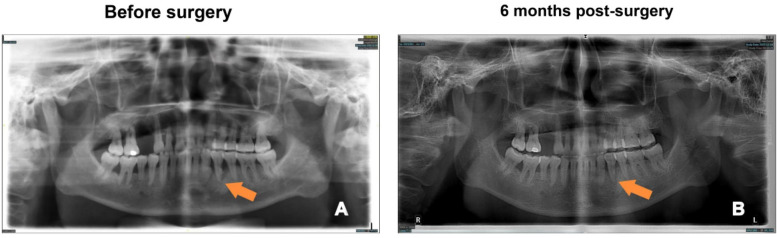

Background: Periodontal flap surgery is a common procedure for treating advanced periodontal disease, but postoperative complications such as pain, infection, and delayed healing are frequent. This study aims to investigate the incidence of postoperative complications and identify key risk factors, contributing to more personalized surgical management.

Methods: A retrospective analysis was conducted on 121 patients who underwent periodontal flap surgery. Patient demographics, clinical data (e.g., age, probing depth, clinical attachment loss), and surgical variables (e.g., incision type, surgery duration) were collected. Logistic regression analysis was performed to identify significant predictors of postoperative complications. The complications analyzed included dentin hypersensitivity, excessive pain, infection, and gingival bleeding.

Results: Postoperative complications occurred in 44.63% of patients. Age was a significant predictor, with each additional year increasing the risk of complications by 12% (p < 0.001). Clinical attachment loss was strongly associated with complications (p = 0.009). Semilunar incisions, typically used in localized mild cases, were associated with a lower incidence of complications compared to trapezoidal incisions (p < 0.001). Smoking also significantly increased the risk of complications in both the univariate and multivariate analyses (p < 0.05). In the univariate analysis, both preoperative antibiotics and preoperative analgesics were associated with a reduced risk of complications (p < 0.05), but these effects were not significant in the multivariate analysis (p > 0.05).

Conclusion: This study highlights age, clinical attachment loss, smoking, and surgical incision type as significant predictors of postoperative complications following periodontal flap surgery. The findings underscore the need for personalized surgical approaches, particularly in older patients and those with severe periodontal disease.